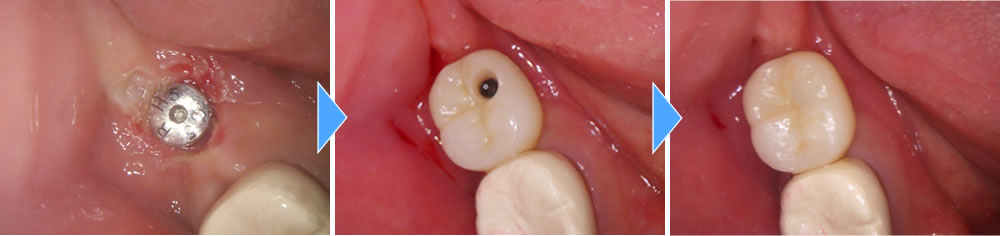

上部構造(人工歯)の装着・治療完了

5ヵ月の待機期間を経て、インプラント体と骨がしっかりと結合したことを確認しました。その後上部構造の型どりをし、上部構造のジルコニアをセットして治療完了となりました。